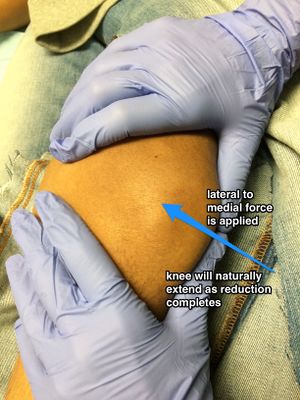

[[File:Patellaluxation ap 001.png|thumb]] | [[File:Patellaluxation ap 001.png|thumb]] | ||

| − | * | + | *Clinical diagnosis |

| − | * | + | *May consider pre-reduction x-ray if concern for fracture (not required) |

- Clinical diagnosis

- May consider pre-reduction x-ray if concern for fracture (not required)

- Reduce; do not need x-rays prior to reduction. Rarely need any sedation though a dose of IV pain medication can help relax the patient

- Option #1:

- Mild flexion of hip (20-30 degrees by raising head of bed, not by propping the leg up off the bed) to relax quadriceps

- Slowly extend and slightly hyperextend the knee and slide patella back into place.

- Option #2

- One provider applies slow downward pressure over the quads. This stretches out the muscle and slowly straightens the leg

- At the same time, second provider pulls gentle traction of the patella outward while rotating the patella back over from lateral to anterior